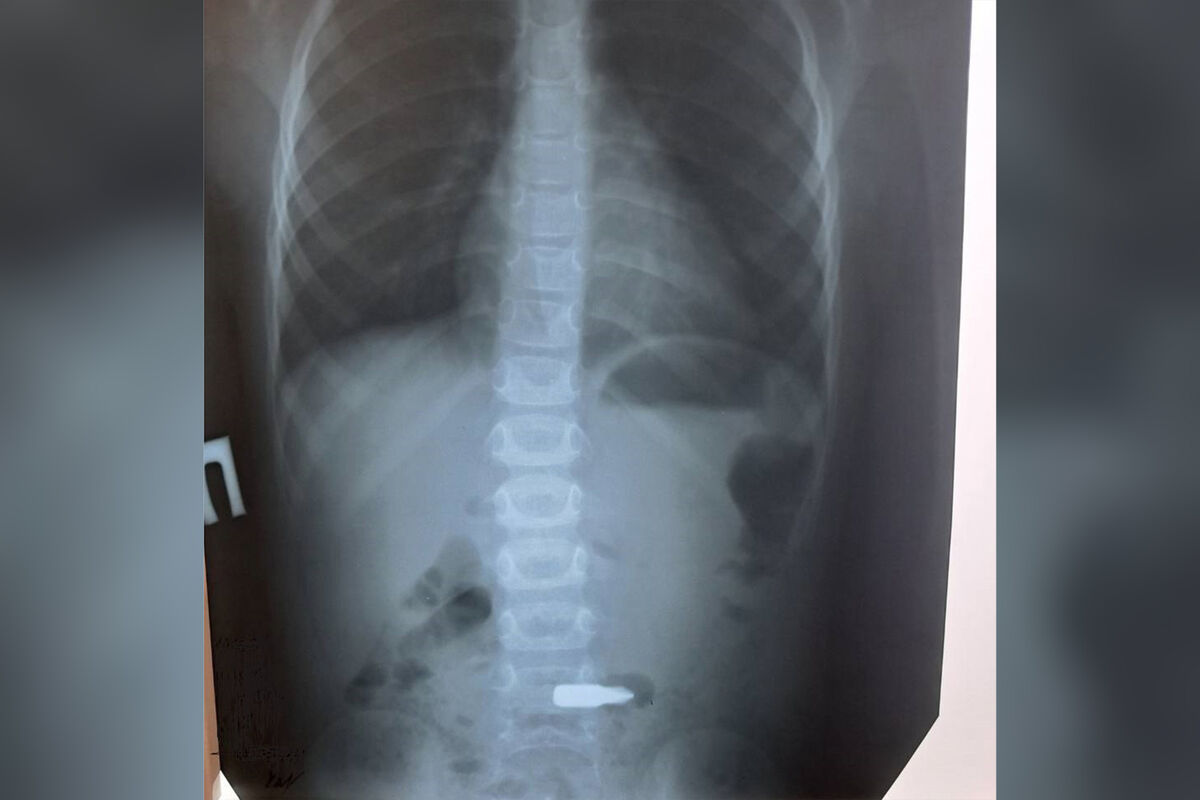

Медики Балаковской городской больницы спасли ребенка, который проглотил биту от шуруповерта. Об этом сообщает пресс-служба медицинского учреждения.

В больницу был доставлен четырехлетний мальчик с подозрением на инородное тело в желудке. Выяснилось, что мальчик проглотил деталь от шуруповерта. Врачи-эндоскописты извлекли биту от инструмента под общим наркозом.

Вмешательство прошло успешно, некоторое время мальчик находился под наблюдением врачей и был выписан на амбулаторное лечение.